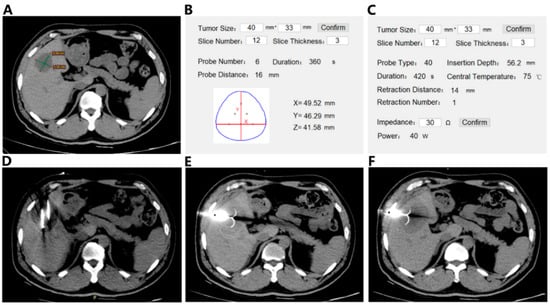

Multi-mode Thermal Therapy: The new multi-mode thermal therapy procedure consisted of a sequential rapid freezing, natural thawing, and radio-frequency (RF) heating of the target tumor tissue. Cryoprobes (CryoHitTM, GALIL Medical, Yokneam, Israel) and an expandable hook-shaped RF probe (MedSphere, Shanghai, China) were used in this clinical study. For surgical planning, a commercial three-dimensional segmentation software (HG-mediGPS-I, Hokai Medical Instrument Co., Ltd., Zhuhai, China) was used to extract the geometry and relative position of the tumor, liver, ribs, and other organs based on MRI images. The segmented geometric model was then imported into the finite element analysis software (COMSOL Multiphysics 5.2) for computation. In the freezing step, the number of cryo-probes, relative distances, freezing power, and time were calculated based on the bio-heat transfer model to assure rapid freezing and to allow the ice ball to cover the entire tumor for 10 min. Natural thawing was allowed for 5–10 min. In the subsequent RF heating, the probe insertion depth, center temperature, heating power and time, and number of staged retreating and distances were calculated based on our previously developed model accounting for the pre-frozen tissue property changes [6,12]. The total RF heating period ranged from 10–15 min, depending on the tumor size. Figure 1 shows the operational procedure of the multi-mode thermal therapy under CT (64-slice CT scanner, Brilliance CT, Philips, Netherland) guidance.

Figure 1.

Operational procedure of the multi-mode thermal therapy: a representative case. (A) The axial CT imaging showing a 40 mm liver tumor in the patient; (B) the plan for freezing; (C) the plan for heating; (D) freezing process using seven cryo-probes (CryoHitTM, GALIL Medical, Israel). The low signal area near the cryo-probes indicating the formation of ice ball; (E) the first step of radiofrequency ablation (RFA), the probe with 4.0 cm active tip (MedSphere, Shanghai, China) inserted to the bottom of the tumor; (F) the staged retreat heating process to make the heating range cover the entire tumor.